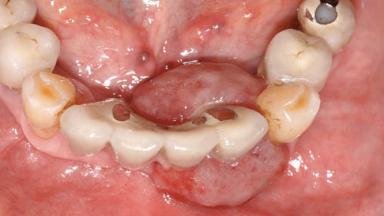

Jaw Mandible

Area Anterior|Posterior

# of Teeth 10

# of Implants 5

Type of Implants One-Piece